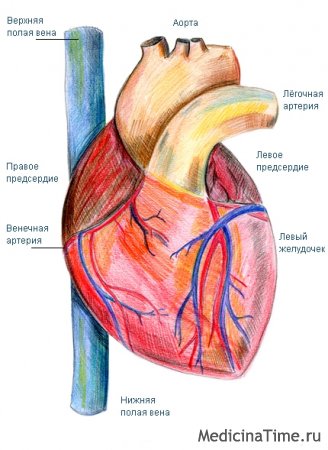

Анатомия Сердца: Расположение и Функции